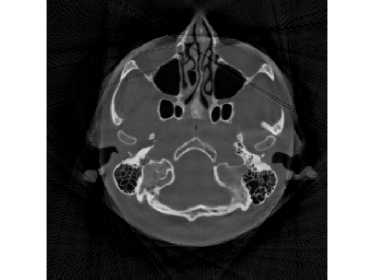

To give an intuitive impression of saturation phenomenon happens in CT scan, a knee phantom is designed in Fig.1. Its 360superscript360360^{\circ} projection data without and with saturation are shown in Fig.1 and 1, respectively. If there is no saturation, then the object can be reconstructed well by classical analytical algorithms, such as the standard filtered back projection (FBP, [5]) or iterative reconstruction methods, such as the simultaneous algebraic reconstruction technique (SART, [6]). When there is saturation in the sinogram data, e.g. Fig.1(d), CT reconstruction from the saturated data is quite hard. For example, directly applying FBP on the saturated data in Fig.1 outputs Fig.1, which is far from satisfactory.

Figure 1: (a) A knee phantom; (b) reconstructed by FBP from saturated projections shown by (d); (c) full projection data; (d) saturated projection data (the measurable range κ=0.5pmax𝜅0.5subscript𝑝\kappa=0.5p_{\max}; see Section V-A for details).